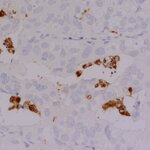

IHC-P (FFPE): 1 : 100 gallery

Immunohistochemistry (IHC-P) of formalin fixed, paraffin embedded (FFPE) tissue (some antibodies require special antigen retrieval steps, please refer to the ”Remarks” section). Immunoreactivity is usually revealed by fluorescence or a chromogenic substrate.

This product belongs to the HistoSure product line of antibodies developed for and extensively tested in FFPE tissues.

For more information please visit our HistoSure brand website.